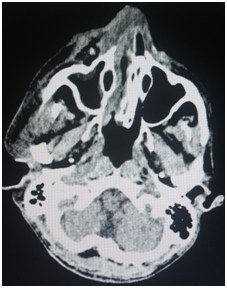

A 48 year old male patient was referred to our outpatient department with history of unsettling facial swelling and uncontrolled diabetes mellitus for which he was hospitalized under the general medicine ward. History revealed that the patient had a fall from the bed in an inebriated state three days prior, following which he developed swelling over the right side of the face and pain in the upper front teeth. In the mean time he was treated by his dentist who extracted the upper right canine and premolar presuming that the swelling in the canine Fossa was caused by dental infection. An intra oral incision and drainage was also performed in order to drain the abscess. On clinical examination he presented with right ‒sided infra orbital swelling with a portion of the overlying skin necrosed. The swelling was seen obliterating the naso labial fold on the same side. Gross edema of the peri‒oral and periorbital tissue with resultant narrowing of the palpebral fissure was noted on the same side (Figure 1). Intraoral examination revealed an extraction socket in relation to upper right canine and premolar and vestibular laceration with slough and poor oral hygiene (Figure 2).

Figure 1 Gross edema of the peri-oral and periorbital tissue was noted on the same side.

The patient was started on intravenous antibiotics which included Piperacillin 2.5 gms and Linezolid 600mg 12 hourly. A combination of Injection Human Actrapid and Insultard were used for his glyceamic control. However, he did not respond to the therapy and the area was severely infected. CT scan revealed the presence of a diffuse soft tissue swelling superficial to the right parotid space extending to the right buccal space with increased density and streakiness of sub cutaneous fat consistent with inflammation. The underlying bone seemed to be unaffected (Figure 3).